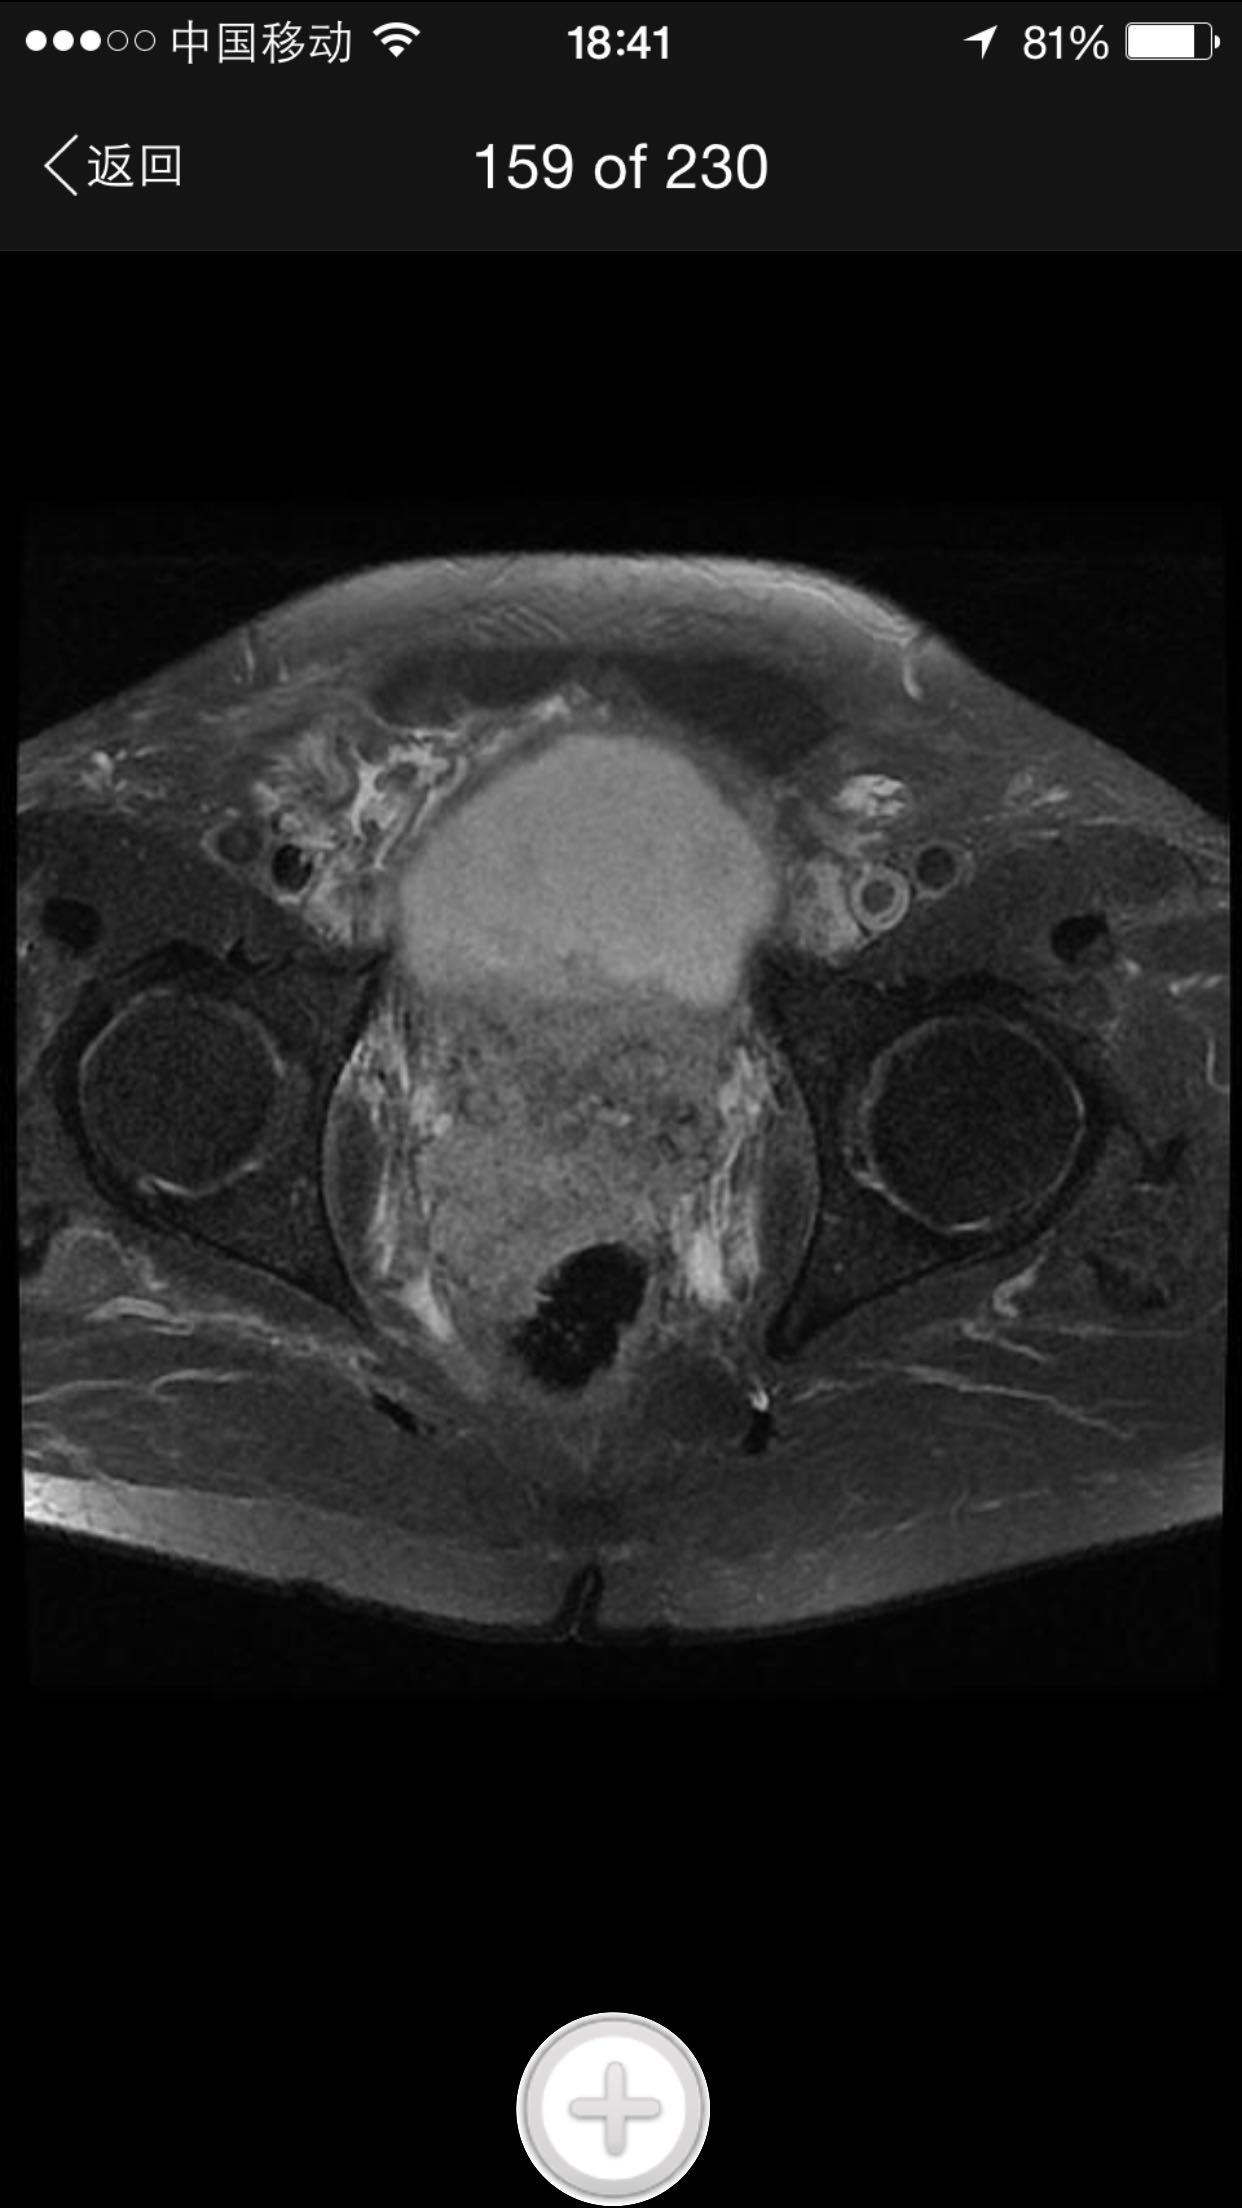

肛诊:前列腺增大,质硬,可扪及多个硬结。 PSA329ng/ml。

诊断:前列腺癌晚期 尿潴留 治疗:考虑患者临床分期较晚,T4期,且淋巴结转移,合并尿潴留,超声提示肾积水,决定行TURP,解决排尿困难。术中快速,如为前列腺癌,直接行手术去势。术中按上述方案处理。术后病理为前列腺中分化腺癌。